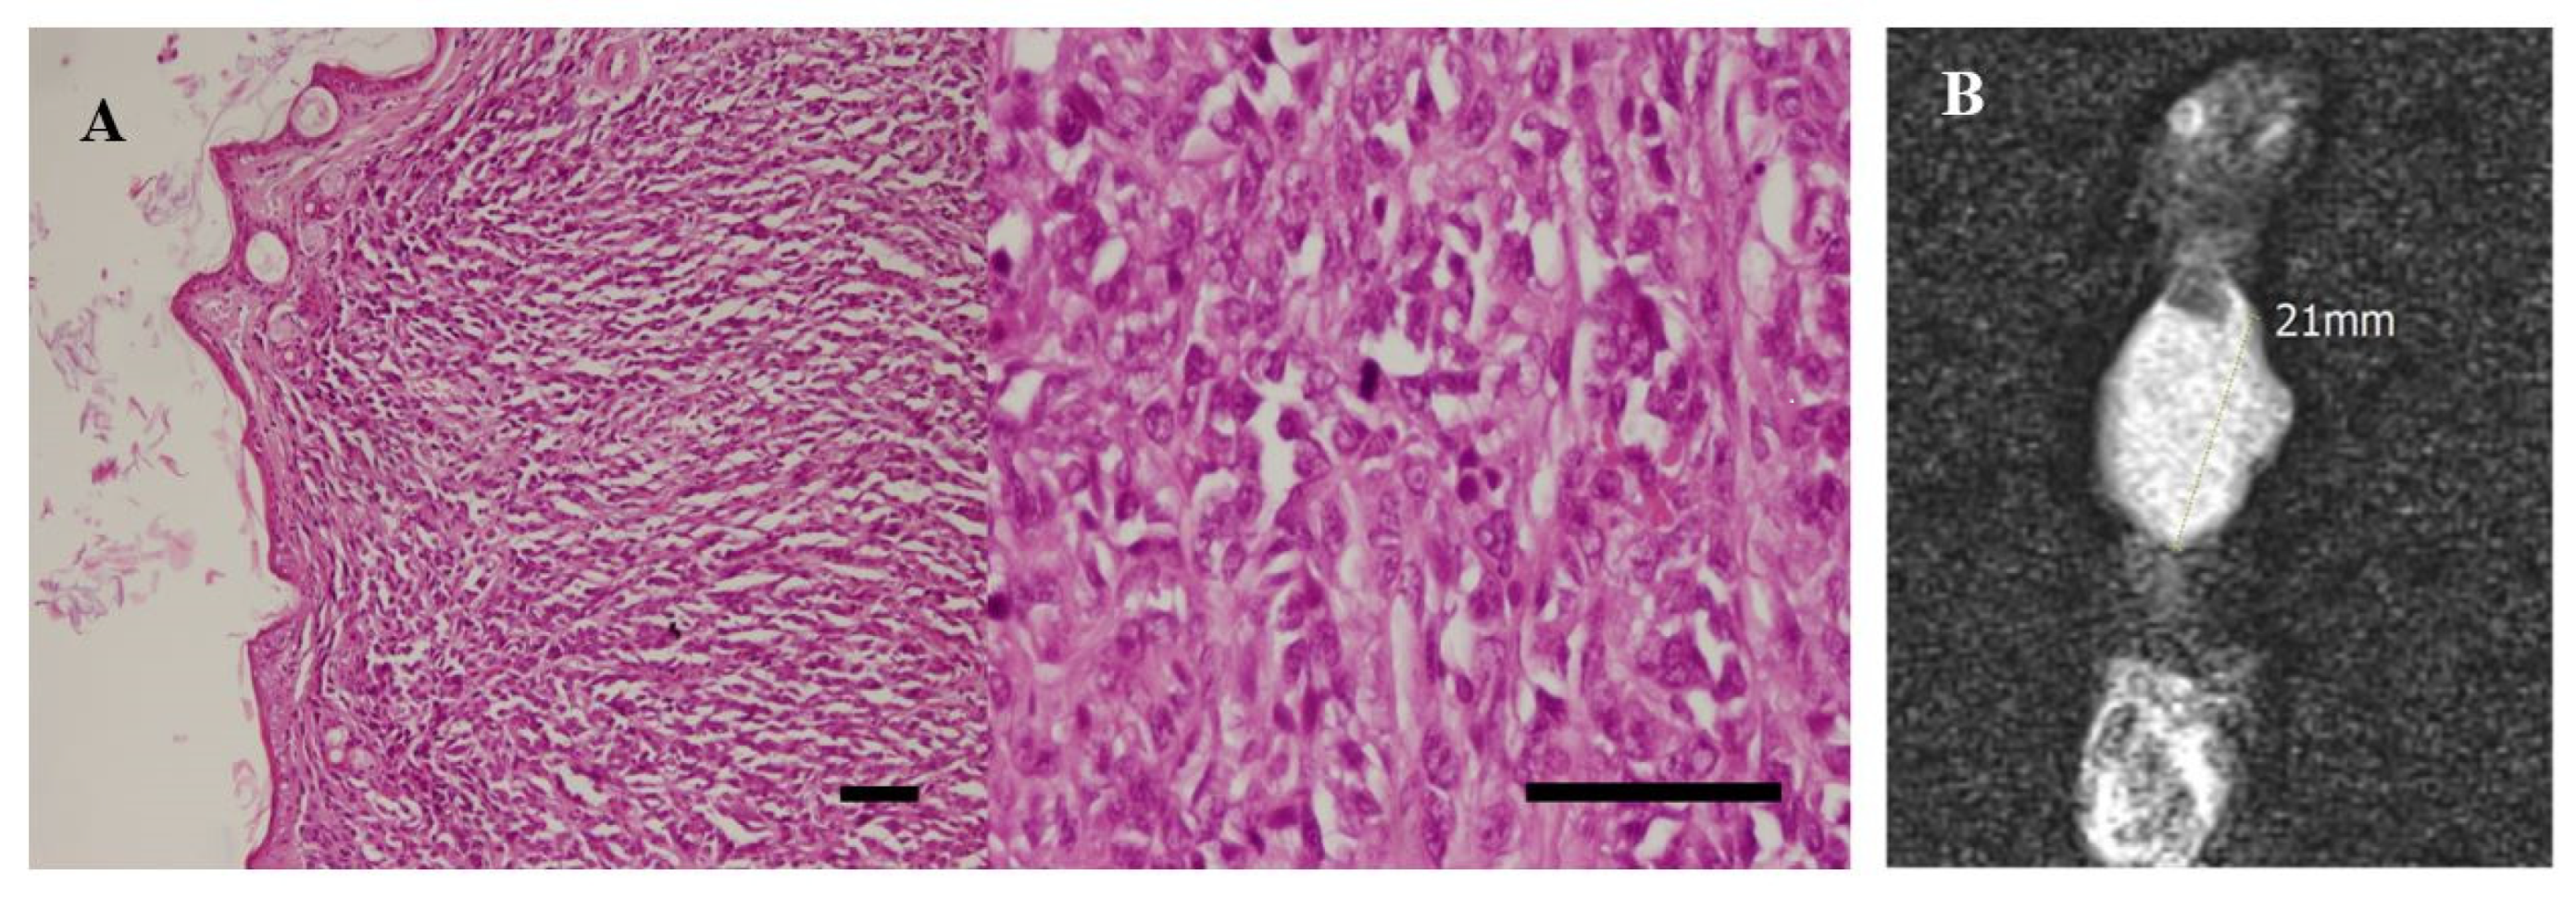

3.5. In Vivo Experiments and MRI Analysis